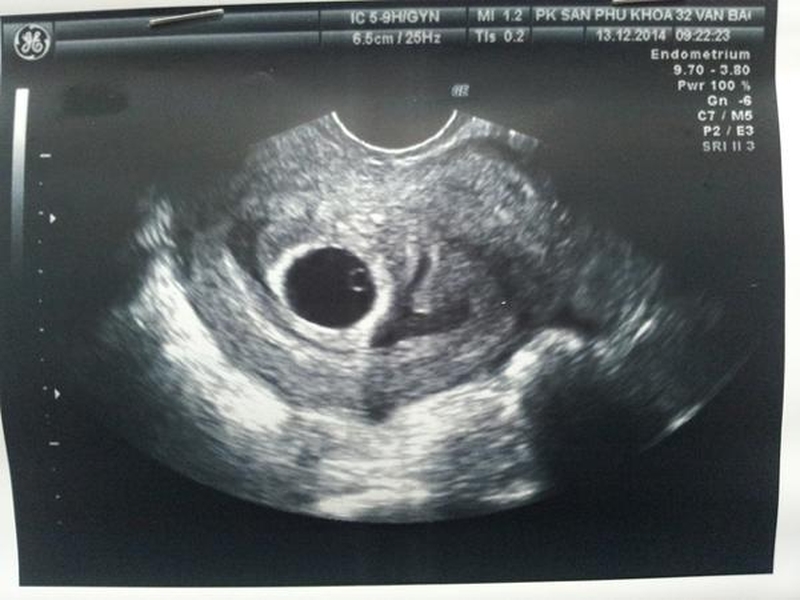

Trong thời kỳ mang thai thì tim thai sẽ hình thành và bắt đầu đập kể từ ngày thứ 22 sau khi thụ thai. Thông thường tim thai sẽ xuất hiện vào tuần thứ 6 đến 7 của thai kỳ thông qua các kỹ thuật siêu âm hiện đại, giúp mẹ có thể dễ dàng nhận biết và nghe được tim thai.

Khoảng thời gian thích hợp để siêu âm tim thai là tuần thứ 6 - 9 của thai kỳ, giai đoạn này sẽ giúp mẹ bầu xác định chính xác mình có mang thai hay không, nhận biết được tuổi thai và đồng thời kiểm tra tim thai có đang hoạt động hay không. Bên cạnh đó thông qua việc siêu âm tim thai sẽ có thể sàng lọc được tình trạng khuyết tật tim bẩm sinh, tim một thất, teo van động mạch phổi,.... Chính vì vậy mà không nên bỏ qua siêu âm tim thai ở giai đoạn này, bởi nếu không thăm khám, không biết được sự phát triển, tồn tại của bé sẽ rất dễ gặp phải những vấn đề không mong muốn.